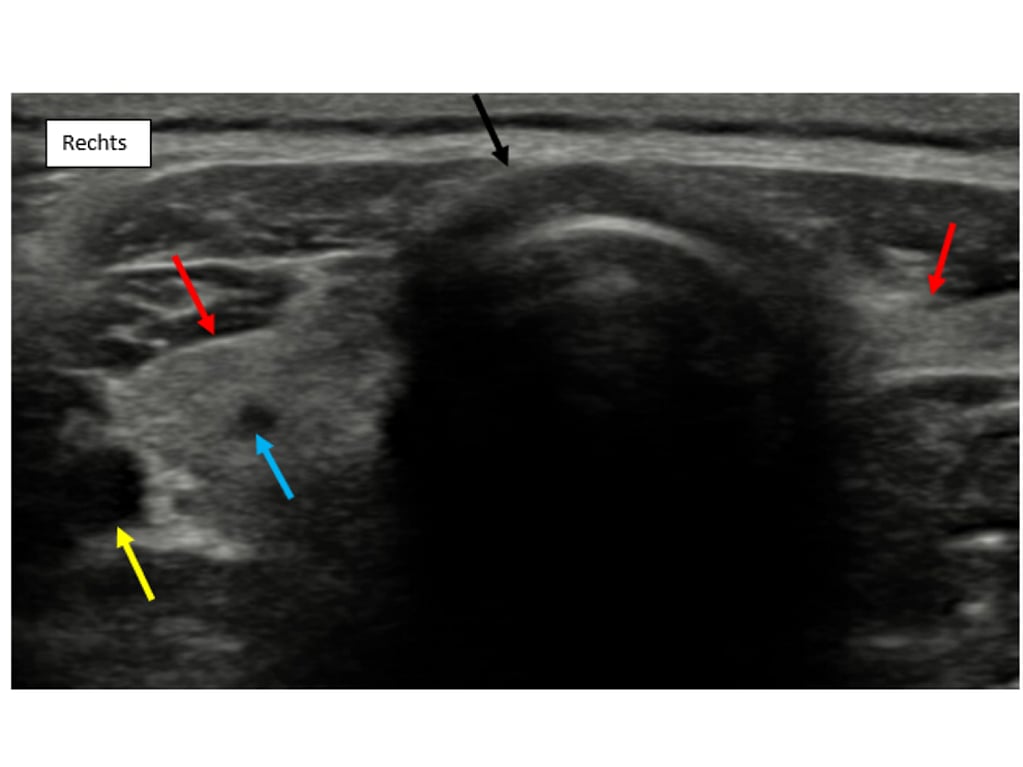

Fig.1. Het transversale echografisch beeld toont de trachea (zwarte pijl) met aan weerszijden de homogeen echorijke schildklieren (rode pijl) gelokaliseerd tussen de trachea en de arterie carotis communis (gele pijl). In de rechter schildklier is een kleine echoarme nodule zichtbaar (blauwe pijl), passend bij een normale bijschildklier.